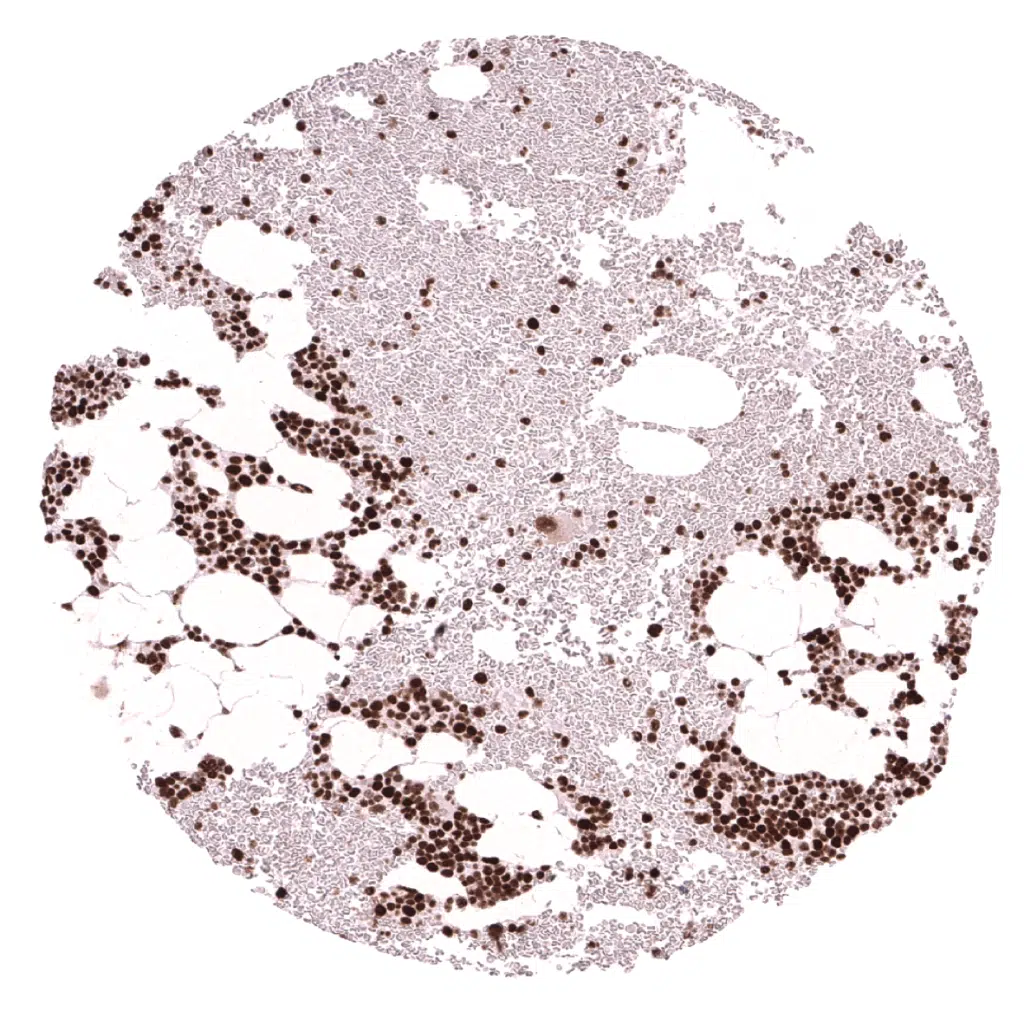

Bone marrow